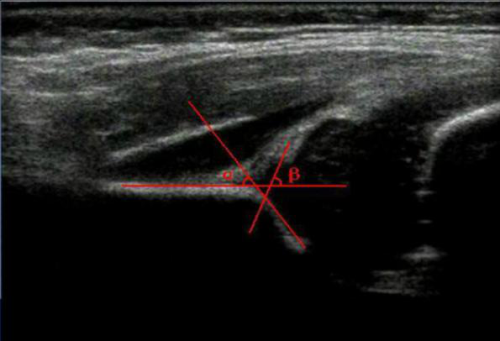

婴幼儿髋关节大部分由软骨成分构成,股骨头尚未骨化,X线检查不能用于早期诊断。而超声检查可以清晰显示尚未骨化的股骨头、髋臼软骨及盂唇等结构,显示股骨头与髋臼的相对位置,直观显示髋关节的软骨及骨性结构,评估髋臼发育情况及股骨头位置。成为婴儿髋关节检查的重要手段,其在很多医学发达的国家和地区已被公认为早期诊断发育性髋关节脱位的首选方法,具有准确性高,无放射性损伤、允许重复操作和跟踪观察等优点。

DDH的治疗关键是早期做出诊断,早期应用正确的治疗方法。而且越早诊断,治疗越容易,结果越安全有效。超声采用Graf法分级来评估DDH的严重程度,从而为临床治疗及监测疗效提供依据,确定最好的治疗方法(如牵引、夹板等)。错过挽救手术时间、术后复发或恢复不佳均可能给患儿造成终身的残疾,影响孩子一辈子。因此早期诊断DDH对于改善治疗结果非常重要,降低手术率,同时降低了并发症发生的风险,小孩半岁以前检查后及时进行治疗,相比患儿开始学步行走后治疗更安全、更成功。